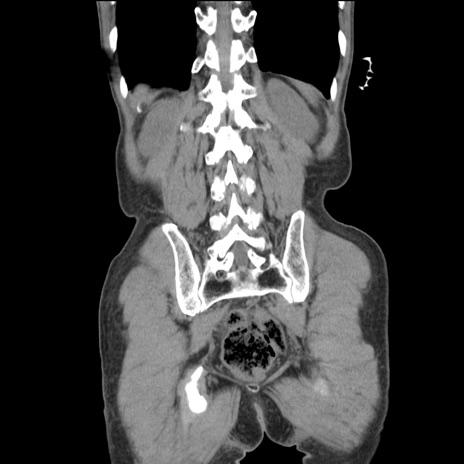

症例11(冠状断像)

【症例】 60歳代男性

【主訴】 下腹部痛

【現病歴】 本日夜中より下腹部痛の症状認め、受診。

【既往歴】 膀胱癌(膀胱全摘+尿管皮膚瘻術) 、胃癌術後

【身体所見】 BT 35.3℃、PR 58/min、BP 136/98mHg、腹部平坦、軟、腸蠕動音±、ストマ留置あり、左上腹部~正中部に圧痛あり、反跳痛なし。

【データ】WBC 5100、CRP0.01